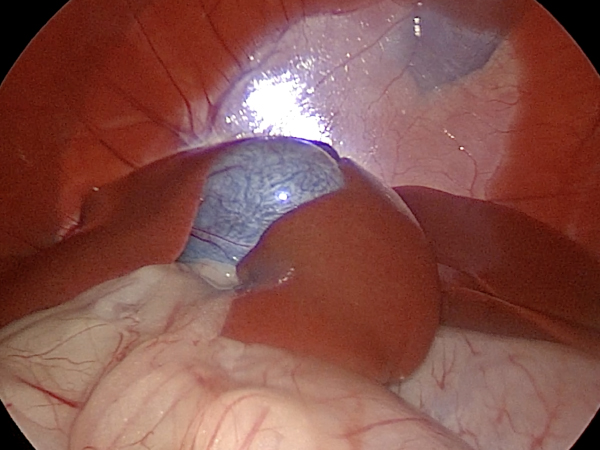

写真のようにお腹に小さな穴をあけて、カメラを挿入し画面を見ながら手術を行います。

傷口も非常に小さく、安全に手術を行うことができました。